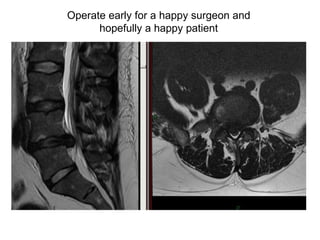

Operate early for a happy surgeon and hopefully a happy patient

Lumbar MRI (sagittal view)

Lumbar MRI (axial view)